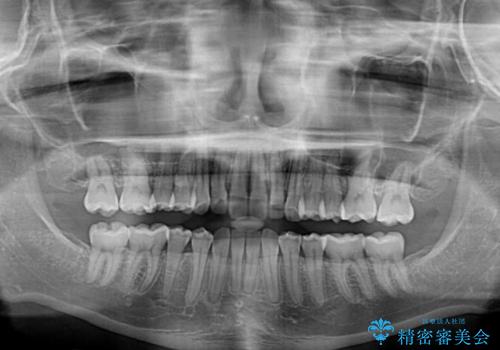

当初は上記計画でしたが、レントゲン撮影よりインプラント埋入は困難と判断され、患者様と相談の上、歯を削ってブリッジとするよりも、奥歯の咬み合わせを多少妥協することとなっても、スペースを閉じて仕上げていくこととしました。

1年弱で治療方針を変更したため、治療期間は長くなりましたが、スペースは無事に閉じ、咬合の違和感なく仕上げることができました。

ただし、両方の臼歯部は理想的な咬合とは言えないため、咬合による歯の外傷を防ぐため、就寝時にはマウスピースを継続使用するようお願いしております。